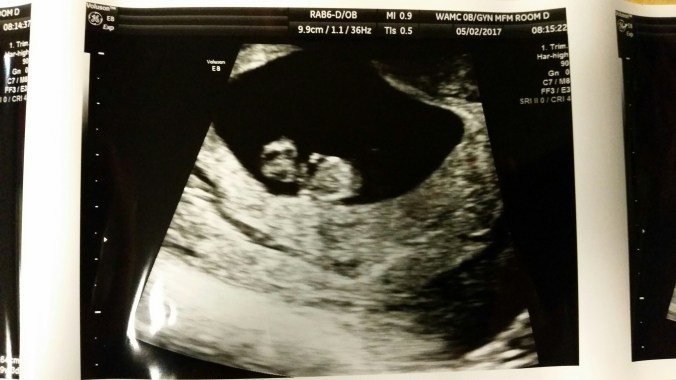

There were still a whole lot of nerves going into our 8 week ultrasound. We were excited to see how much the baby had changed but so afraid that little heart might not be beating any more.

Our perfect little seahorse baby at 8w1d measuring exactly 8w1d. HR 158. Baby read the book the first 2 weeks.